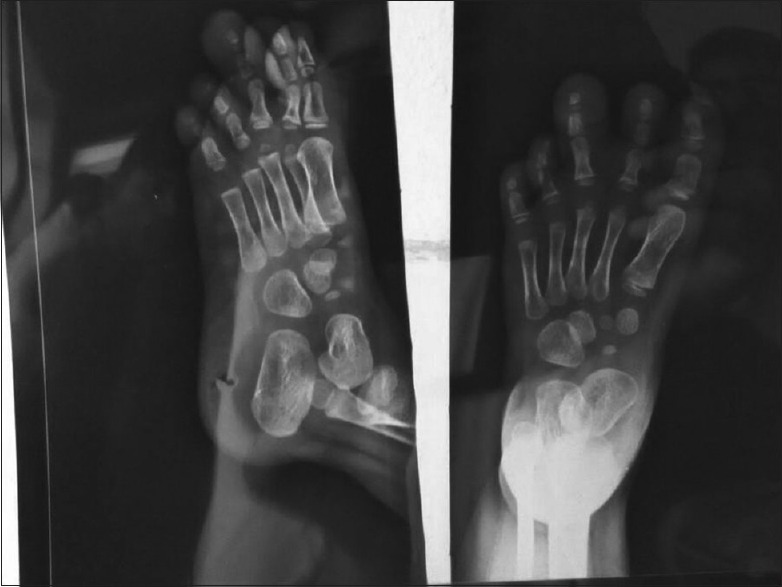

A 21-year-old right hand dominated female presented with a progressive disproportionate enlargement of distal arm and digits of the right hand since birth. The patient denied having any pain or neurovascular symptoms, and there was no family history of extremity gigantism. Twelve years back, she had a history of amputation of index and middle fingers at some periphery hospital. However, no records of the same were available. On physical examination, a nontender, soft-tissue mass was palpable on the volar aspect of the enlarged thumb with disfigurement of digits and distal arm [Figure 4]. There were no overlying cutaneous changes, pitting edema, or bruit. A plain radiograph demonstrated soft-tissue swelling along the volar aspect of the thumb, enlarged phalanges of the digits [Figure 5]. Gray-scale ultrasound and color flow Doppler revealed diffuse soft-tissue thickening, without any abnormal calcifications or abnormal blood flow. Fine-needle aspiration from the disproportionate areas yielded blood-tinged fatty aspirate. Smears examined revealed fragments of mature adipose tissue. No malignant cells were identified. No other spindle cell component was identified. The background revealed fat droplets admixed with RBCs and few inflammatory cells. Correlating the lesion's clinical presentation, imaging and cytological finding possibility ML was considered. The multidisciplinary team decided to perform a debulking surgery. On gross examination a yellowish soft-tissue mass was received which on cut section was fibrofatty. No firm areas or hemorrhage or necrosis was identified. Microscopic examination revealed mature fibroadipose tissue involving the subcutaneous plane [Figure 6]. The nerve sheath and the surrounding muscle fibers were free of fatty infiltration. Thus, a definitive diagnosis of ML was rendered which confirmed the initial possibility.

| Figure 5:X-ray image showing bulbous enlargement of the thumb of the right hand